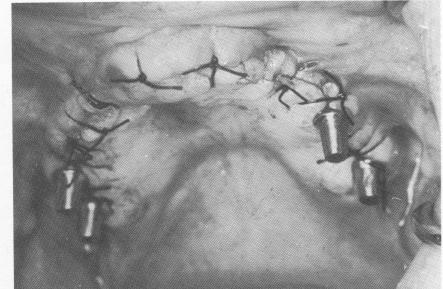

Fig. 11-182. The tissues are carefully sutured together.

2 Tissues sutured after palatal horseshoe type blade inserted in maxilla